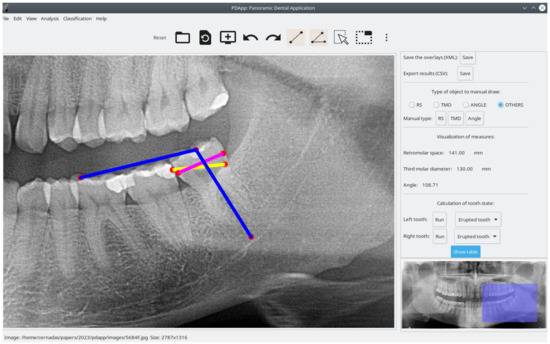

The software is reliable and precise because it allows reviewing the classification of mandibular third molars. Figure 5, image (a) shows a case of a third molar that is classified as erupted by PDApp and image (b) a posterior panoramic radiograph images confirms the PDApp results. It is also easy to use and install. Another advantage that the program offers compared with manual quantification is the possibility of sharing the images and results among other experts to evaluate each case, reducing the variability among experts.

Figure 5. Visual example of correct prediction The pink line represents third molar diameter, the yellow line represents retromolar space, and blue lines represent the angle of eruption: image (a) shows partial retained third molar is classified as erupted tooth by the software; image (b) confirms the eruption of third molar (panoramic one year later). The screenshots have been taken using the windows version of PDApp.